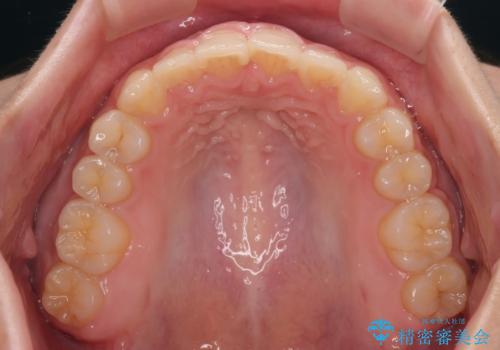

捻れて前に出ている前歯 ワイヤー装置での非抜歯矯正

- 捻れて前に出ている上顎前歯と全体的なデコボコを気にして来院された患者様です。

口元の突出感は強くなかったため非抜歯矯正での対応となりますが、捻転を改善する際に上顎前歯が前突する可能性があったため、上顎臼歯部にアンカースクリューを使用して、歯列が前方に転位しないようにすることとしました。

また舌のトレーニングを行うことで、上顎前歯の突出予防や上下前歯に隙間ができなくなるようにしました。